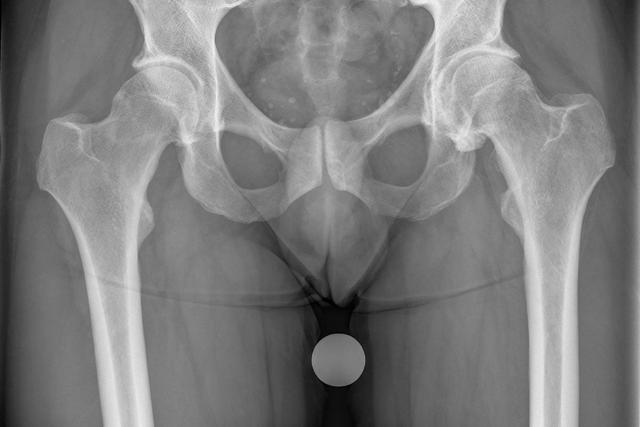

Bei einer Hüftoperation wird in den meisten Fällen eine Totalendoprothese (TEP) verwendet, bei der sowohl die Gelenkpfanne als auch der Gelenkkopf ausgetauscht werden. Die Methode kann entweder zementfrei oder zementiert sein. Beide Methoden haben ihre Vor- und Nachteile, wobei die Entscheidung von Faktoren wie dem Alter des Patienten und eventuellen Risikofaktoren abhängt.

Bei einer Hüftoperation wird in den meisten Fällen eine Totalendoprothese (TEP) verwendet. Etwa 80 Prozent der Operationen erfolgen mit zementfreien TEPs, während die zementierte Methode ebenfalls gut ist. Die Entscheidung für die Art der Prothese hängt von verschiedenen Faktoren ab, wie dem Alter des Patienten und eventuellen Risikofaktoren.